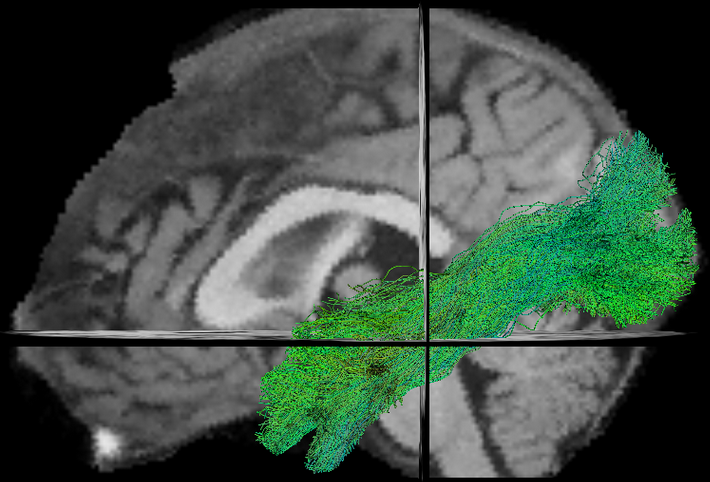

- TractQuerier (Wassermann et al. 2016)

Dictionary

Atlas

Caudate.left |= 11

Caudate.right |= 50

Putamen.right |= 51

Pallidum.right |= 52

Hippocampus.right |= 53

Amygdala.right |= 54

Insula.right |= 55Dictionary

Insula.right |= 55Queries

cc_superiotemporal =

superiortemporal.left

and superiortemporal.right

not in subcortical.left

not in subcortical.right

not in cerebellum